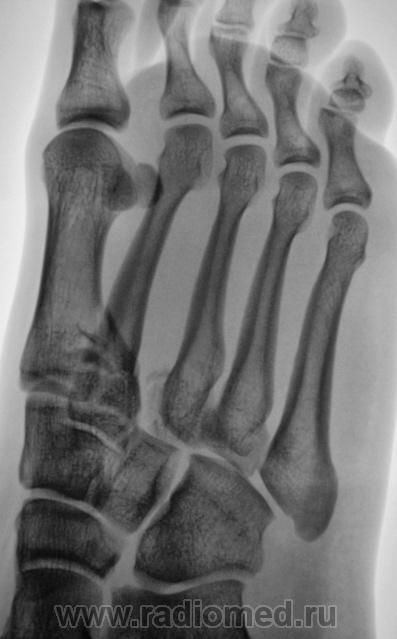

Неделю тому, пациент после ДТП был доставлен в рентгеновский кабинет. Было сделано много, в том числе был и заказан голеностопный сустав. Однако, в голеностопе патологии выявлено не было. Пациент находился в хирургическом отделении, и все, в принципе, нормально было, но вот предъявлял пациент жалобы на боли ... в стопе. Стопа отёкшая, болезненная при пальпации. Сегодня пациента направили на рентгенографию стопы с диагнозом...."Растяжение связок"..?

Произведена рентгенография в стандартных проекциях.

Вот, какие дела...с растяжением.

Хорошее растяжение,  вот только перелом основания 1,2 и 3 плюсневых костей не в счётМолчу-молчу!.

Молодец, хорошо косточки "растянул"